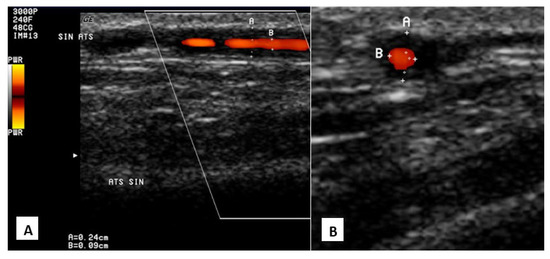

Analysis of Treatment Influence on Kidney Function and Brain Non-Contrast MRI Vascular Manifestations of Systemic ANCA-Associated Vasculitis with Renal Involvement

Background: Antineutrophil cytoplasmic antibody-associated systemic vasculitis (AAV) most often involves the kidneys, upper airways and lungs, and peripheral and central nervous systems (PNS, CNS). However, in contrast to PNS, the involvement of the CNS is rarely taken into account in the recognition and assessment of systemic vasculitis, probably because of nonspecific symptoms such as headaches and dizziness, aphasia, memory disorders, or mood changes. In addition, it is not clear whether treatment of systemic vasculitides reduces cerebral vascular alterations. In this study, we aimed to evaluate the effects of AAV treatment on vascular and vasogenic alterations in the brain in patients with acute vasculitis onset with renal involvement. Methods: Twenty-nine patients (17F, 12M, age 60.4 ± 9.8) with AAV relapse with renal involvement were included in the study. The initial baseline assessment and the second evaluation, performed 12.6 ± 2.5 months after the beginning of immunosuppressive treatment, included clinical, neurological, and renal function assessments, along with a brain MRI. Results: Compared with baseline, improvement in clinical, neurological, and renal function was observed during the second clinical evaluation. A significant reduction in the occurrence of vascular dilatation and narrowing in secondary (37.9% vs. 17.2%; p = 0.031) and tertiary (37.9% vs. 10.3%; p = 0.008) cerebral vascular branches was observed. However, the number of vasogenic cerebral white matter lesions detected on the FLAIR sequence increased significantly (36.0 vs. 48.0%; p < 0.001). Conclusions: Intensive immunosuppressive treatment of acute-onset systemic AAV with renal involvement decreases disease activity, improves kidney function, and decreases central nervous system vascular but not vasogenic alterations. Full article